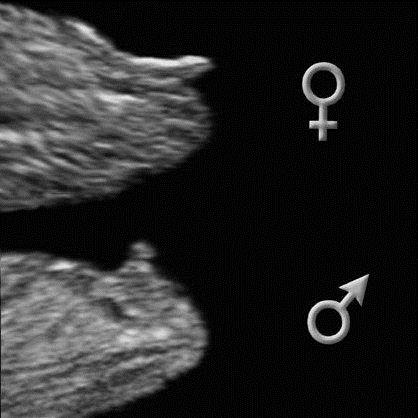

На 12 тижні помітних відмінностей між статевими органами хлопчика і дівчинки немає. Статевий горбок і статеві складки оточені зовні губно-мошоночних горбками.

Хлопчик зліва і дівчинка справа. Погодьтеся, картинки не сильно відрізняються?

Хлопчик - 13 акушерських тижнів

Розвиток чоловічих зовнішніх геніталій залежить від дігідротестерон, який виробляється яєчками. Оскільки статевий горбок подовжується і росте, формуючись в пеніс, сечостатеві складочки, які знаходяться по обидва боки сечостатевої мембрани, починають зростатися, формуючи сечовипускальний канал. Губно-мошоночние горбки посилено ростуть і перетворюються в мошонку, зростися по середній лінії.

На цій стадії розвитку яєчка розташовані в животі. Вони не опускаються в мошонку (6) до сьомого-восьмого місяця вагітності.

Зміни в розвитку статевих органів дівчаток

Статеві органи дівчаток формуються з тих же складочок і горбків, що і статеві органи хлопчиків.

Губно-мошоночних горбки і статеві складочки зростаються і утворюють малі (7) і великі (4) статеві губи. З статевого горбика формується клітор (3). Статевий бульба сформує клітор (3).

Визначення відбувається за рахунок аналізу кута між статевим горбком і спинкою малюка.

Досвідчені УЗД фахівці можуть визначити стать, вимірявши кут статевого горбка.

На 13 тижні відсоток помилки становить приблизно 50% (з 100 хлопчиків точно підлогу визначено у 14), на 16 тижні визначення статі вже більш точне.